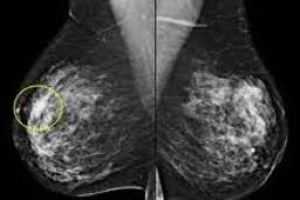

Узловая мастопатия

Статья для справочника портала Медихост

medihost.ru/glossary/diseases/uzlovaya_mastopatiya...